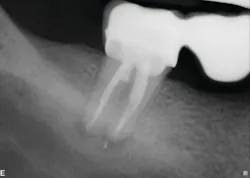

Healing is noted on the six-month follow-up (figure 4).